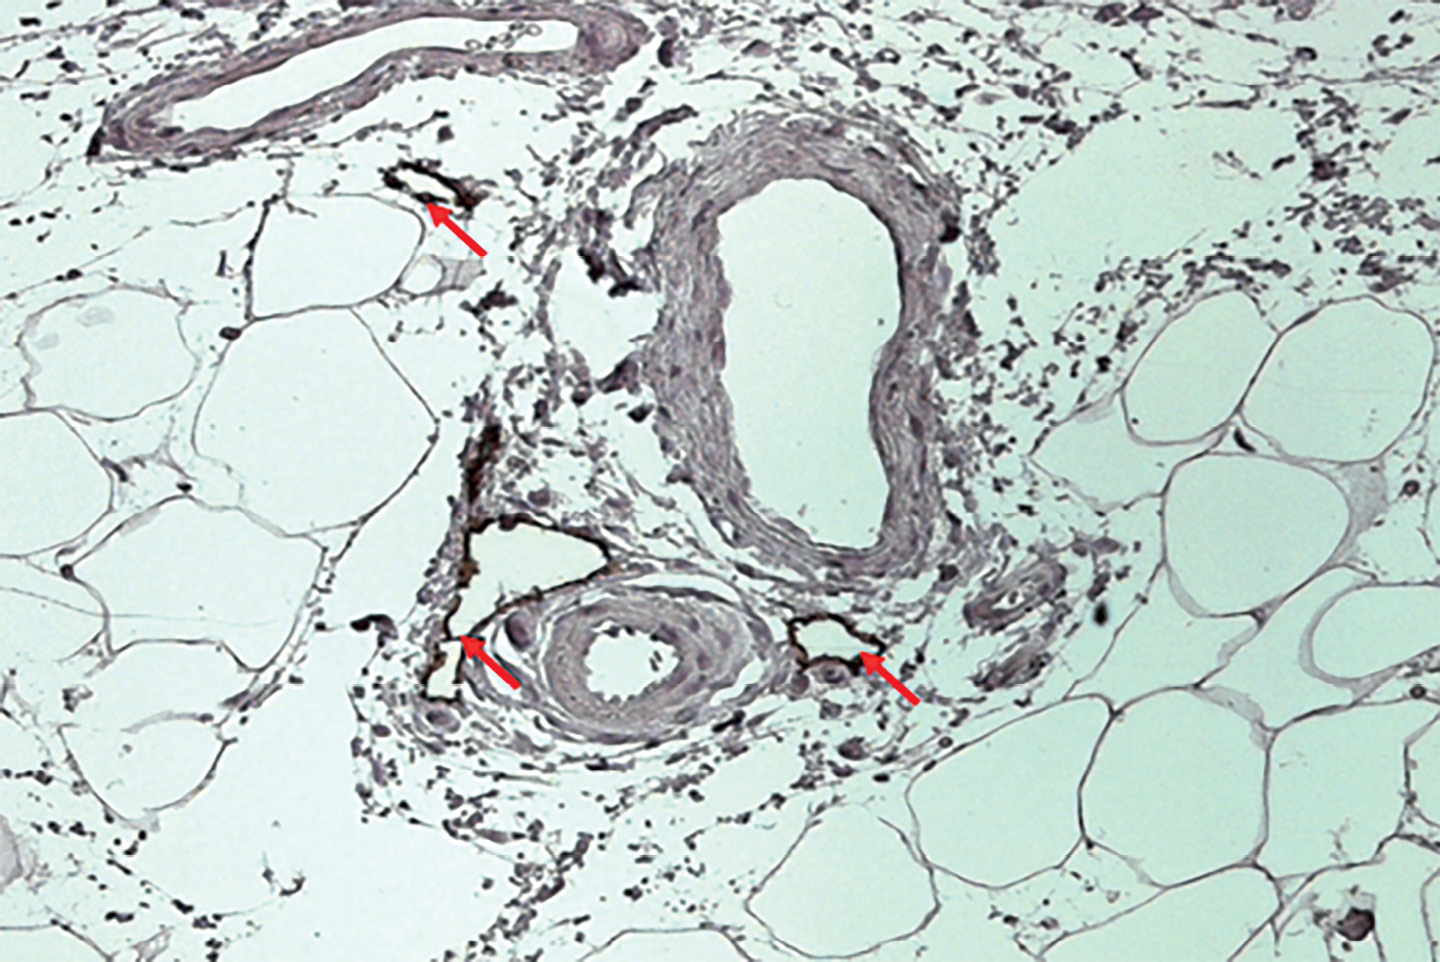

Лимфатические сосуды в ЖТ, как правило, располагаются в прослойках междольковой рыхлой волокнистой соединительной ткани, по ходу кровеносных сосудов (рис. 1). Корнями ЛС являются слепо начинающиеся лимфатические капилляры. Эти высокопроницаемые сосуды состоят из одного слоя эндотелиальных клеток, не имеют базальной мембраны и характеризуются прерывистыми, «пуговичными» межклеточными соединениями. Градиенты гидростатического давления, действующие через лимфатическую стенку, облегчают открытие или закрытие этих соединений, функционирующих как первичная клапанная система [6]. Во время лимфообразования интерстициальная жидкость, содержащая воду, растворенные вещества и иммунные клетки, первоначально транспортируется в просвет лимфатических капилляров. Лимфа, образующаяся в капиллярах, затем пассивно транспортируется в собирательные сосуды, которые разделяются внутрипросветными двустворчатыми клапанами. Эти области собирательных сосудов дополнительно покрыты базальной мембраной и лимфатическими мышечными клетками. В отличие от лимфатических капилляров, эндотелиоциты в собирательных сосудах образуют непрерывные «молниеобразные» межклеточные соединения, предотвращающие утечку лимфы во время транспортировки. Регулирование открытия и закрытия внутрипросветных клапанов поддерживает однонаправленный транспорт лимфы и предотвращает обратный отток [1].

Рисунок 1. Визуализация лимфатических сосудов в подкожной жировой ткани у человека.

Стрелками показаны лимфатические сосуды в междольковой рыхлой волокнистой соединительной ткани. Иммуногистохимическое окрашивание на подопланин. Ув. х100.